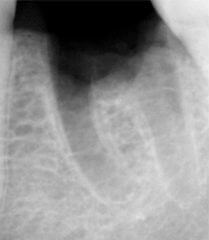

Probleem. Sügav karioosne õõnsus

Lahendus. Kanalid puhastati, valmistati ette täidiseks ja tehti hambaravifoto koos täitematerjaliga.

Sulge hamba juurekanalid. Hammas on valmis edasiseks raviks.